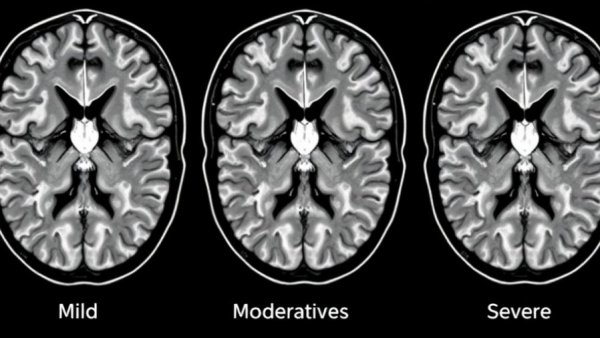

MRI scans showing stages of cerebral small vessel disease.

Statistics reveal that around 95% of older adults aged 60 to 90 exhibit signs of CSVD on brain MRIs, according to medical studies. This alarming statistic raises essential questions: How can families recognize the signs? What preventative measures can be taken? Understanding CSVD is crucial for seniors and their caregivers as it often correlates with balance problems and has been identified as a significant risk factor for various forms of dementia.

If you or a loved one may be experiencing symptoms related to CSVD, don’t hesitate to consult with your healthcare provider. They may recommend neurological assessments or MRIs to determine whether CSVD is present. Early intervention can lead to more effective management and better outcomes.